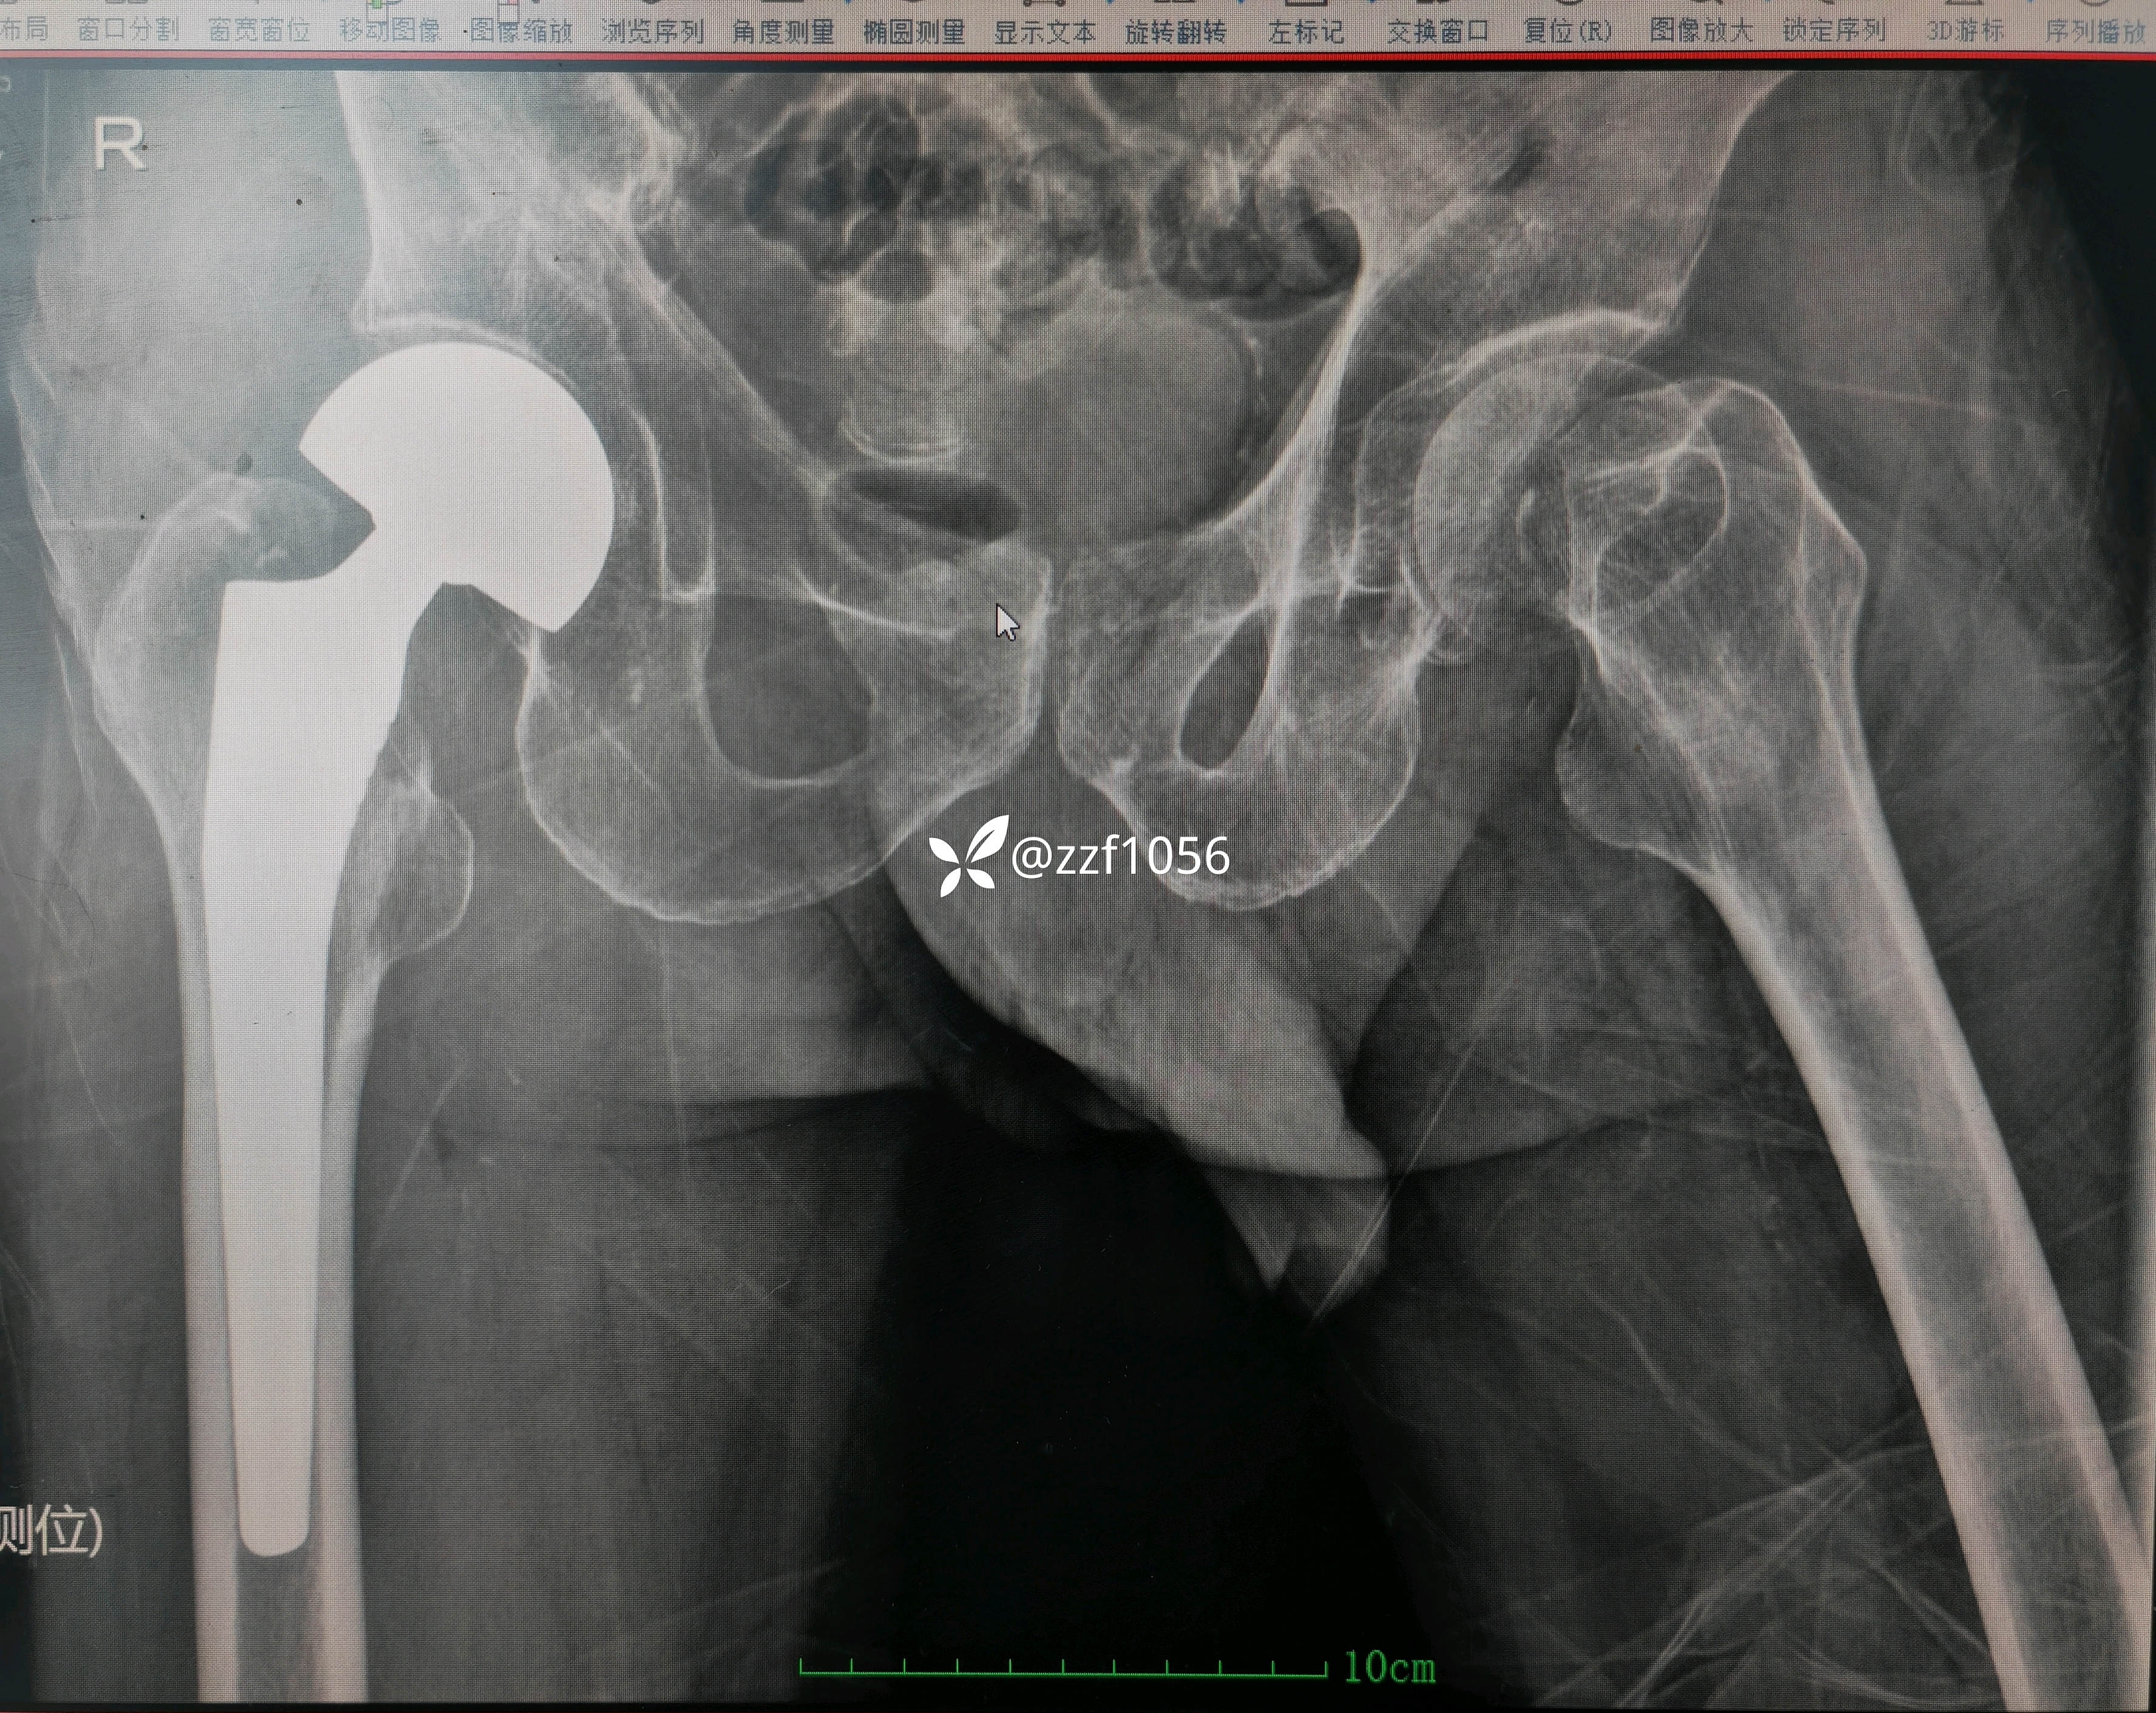

做了一次深入沟通,患者终于统一的意见要求手术,录音录像并所有家属签署特殊形式的知情告知书。

顺利实施手术双动头置换